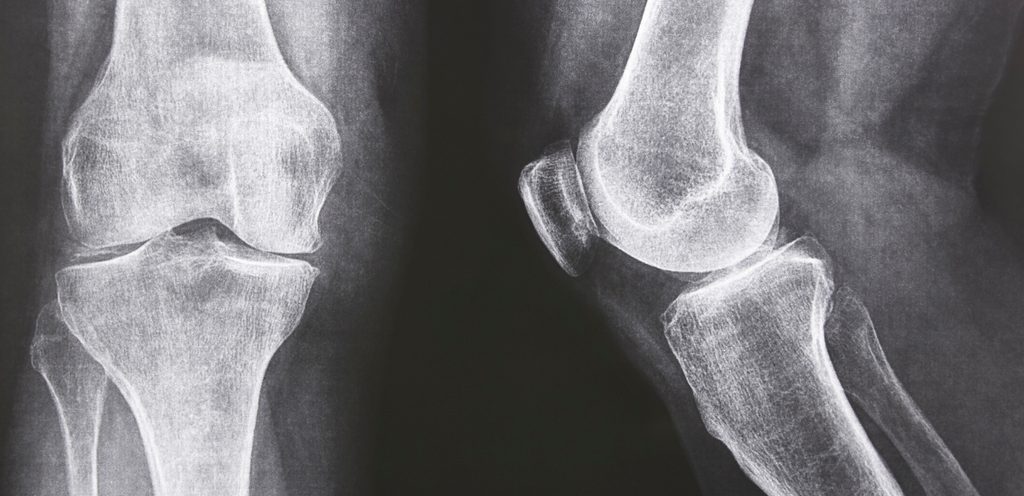

يُعدّ تناول الأطعمة التي تزيد السائل الزلالي في المفاصل من الأمور الحيوية للحفاظ على صحّة الإنسان، حيث يؤدّي هذا السائل دورًا أساسيًا في تسهيل حركة المفاصل ومنع الاحتكاك بين العظام الذي يُسبب ألم الركبة المفاجئ.

- آلام المفاصل: يسبب نقص السائل الزلالي احتكاك العظام ببعضها البعض ممّا يؤدي إلى الشعور بآلام حادة.، فوفقًا لموقع Verywell Health في مقالة نُشِرَت العام الماضي تحت عنوان “Improving and Increasing Synovial Fluid”، السائل الزليلي هو سائل كثيف يشبه قوامه بياض البيض، يساعد في تليين المفاصل وتقليل الاحتكاك بينها، ومع التقدم في العمر، ينخفض مستواه، ممّا يمكن أن يؤدّي إلى تصلّب المفاصل ومواجهة مشاكل أخرى مرتبطة بالشيخوخة مثل هشاشة العظام. ولمعرفة المزيد من التفاصيل عن هذه المقالة يمكنكِ الضغط هنا.